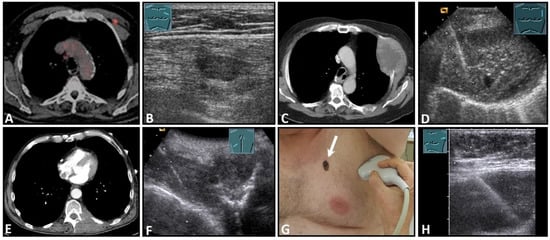

US is of high importance in the detection of malignant lesions due to its location in the near-field region. In addition to imaging, US-guided biopsy is an essential pillar of diagnostics (Figure 9).

Figure 9.

Imaging of four patients with secondary malignant chest wall lesions. Positron emission tomography computed tomography (A) (provided by Prof. Dr. med. Markus Luster, Marburg, Germany) in a patient with small cell lung cancer and focal lesion on B-mode US in the chest wall (B). A patient with metastasis of an esophageal carcinoma: imaging on CT (provided by Prof. Dr. Andreas H. Mahnken, Marburg, Germany) (C) and B-Mode US with visualization of the needle reflex on US-guided biopsy (D). Paravertebral metastasis of vocal fold carcinoma with imaging on CT (E) and B-Mode US with visualization of the needle reflex on US-guided biopsy (F). Imaging of malignant melanoma in the pectoral skin region (arrow) (G) with regional lymph node histologically confirmed as melanoma metastasis (H).